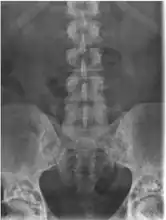

Melorheostosis

- Melorheostosis